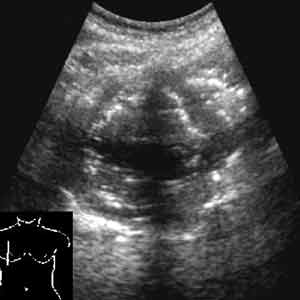

Эхография в диагностике заболеваний легких у детей.

Рис. 7. Абсцесс легкого.

Новости лучевой диагностики 2002 1-2: 56-60